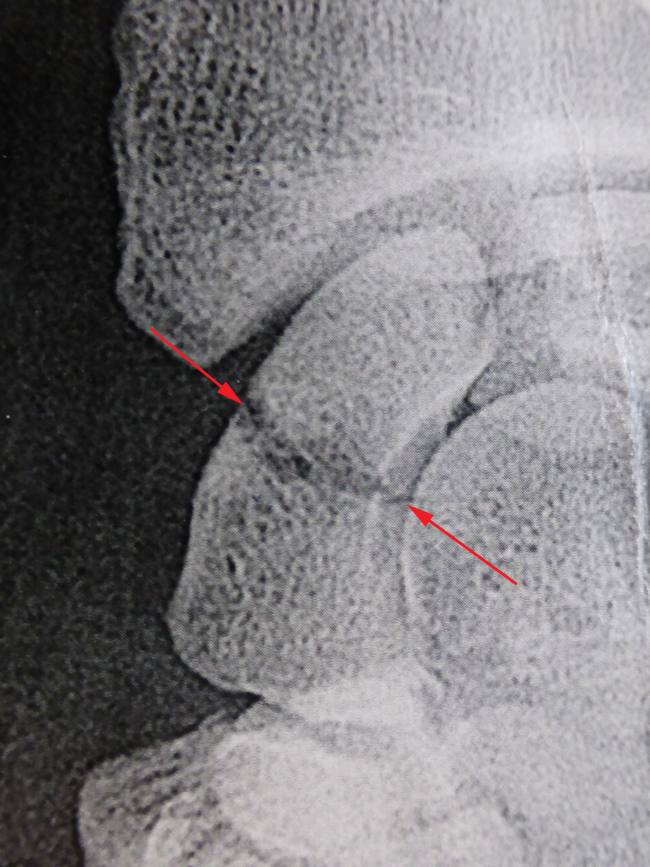

Fractures du pôle proximal du scaphoïde

Ces fractures sont particulières car le pôle proximal du scaphoïde est la partie du scaphoïde qui consolide le plus difficilement. Il est maintenant admis que ces fractures doivent toujours être fixées chirurgicalement, même si elles ne sont pas déplacées. On utilise habituellement une ou deux vis.

Malgré une bonne fixation le taux de non consolidation n’est pas de 100 % et justifie une immobilisation prolongée.